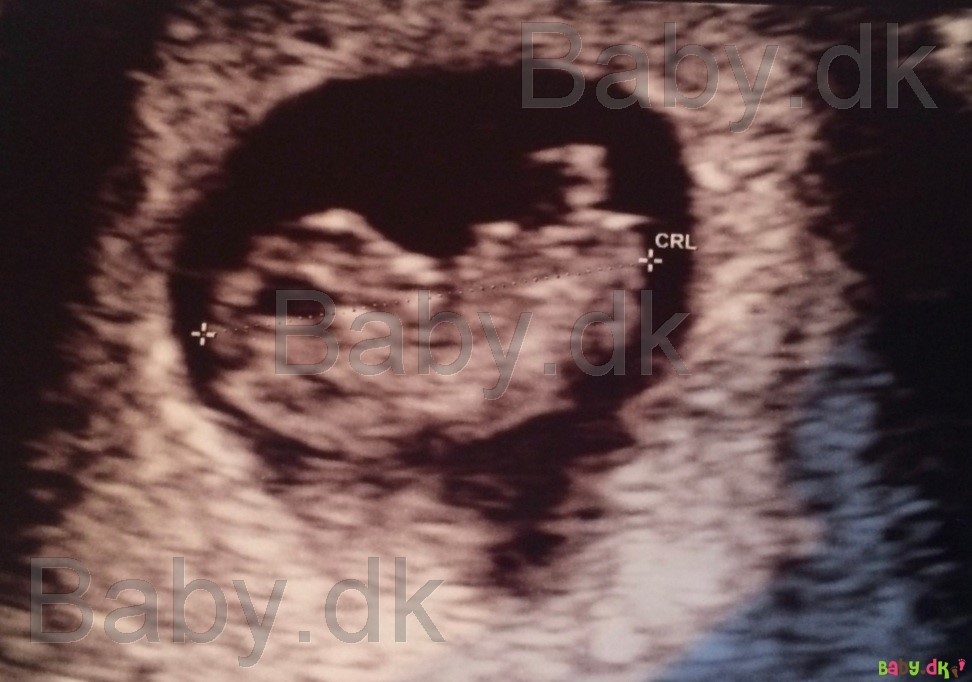

Jeg ved ikke hvor meget det er, du gerne vil kunne se, men jeg vedhæfter lige et billede fra en af mine graviditeter 9+0

Vedhæftede fotos (klik for at se i fuld størrelse)